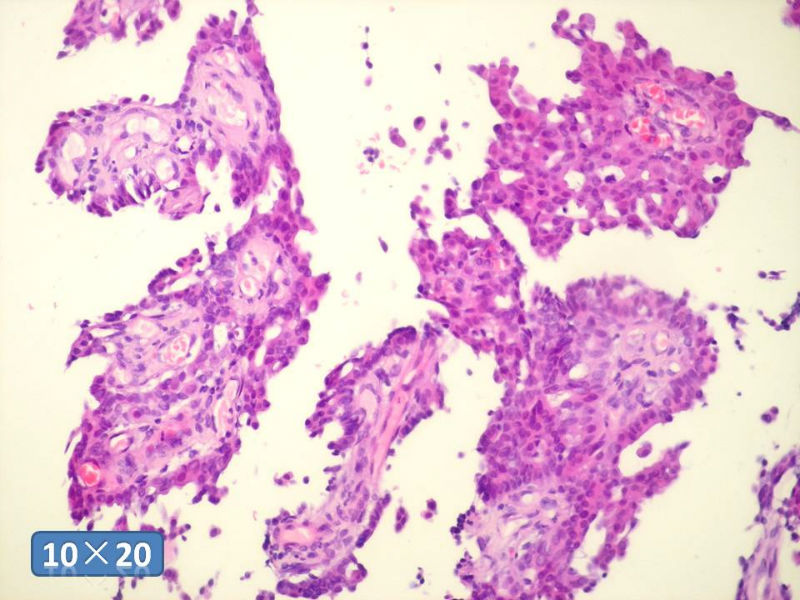

只能说是乳头状瘤

是不是导管内

乳头状瘤 and 导管内乳头状瘤 are the same; Benign lesion.

After you work up and you still cannot be sure it is benign , atypical or maignant lesion, you can call 乳头状lesion.

If this is excisonal case, you should figure out the nature of the papillary lesion.

我的意思就是提醒大家 在不是很确定的情况下 尽量少给自己套枷锁